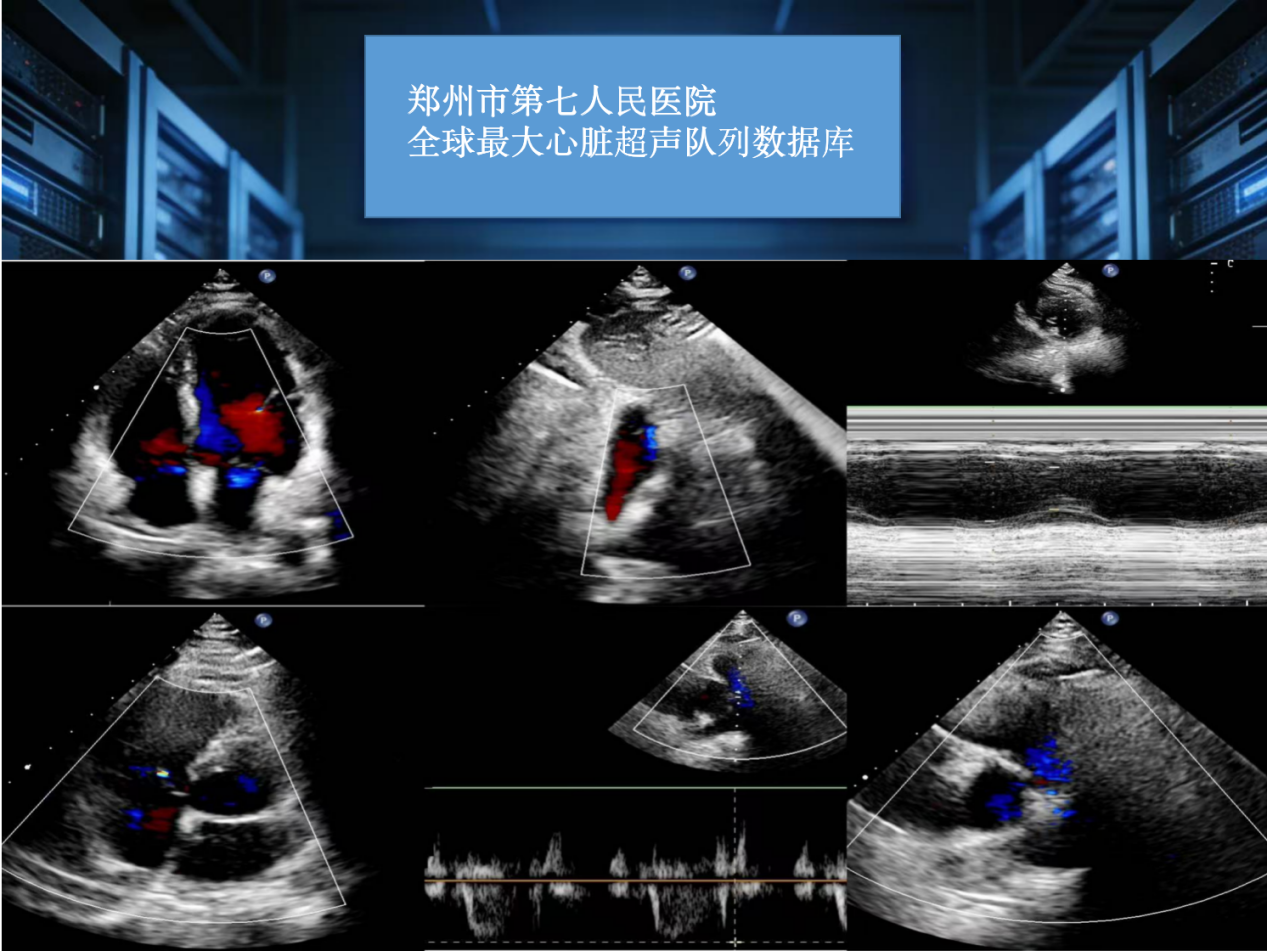

大河网讯 依托15万例真实临床患者数据支撑,聚焦心血管病理影像智能化解析与结构化报告输出,全球最大队列心脏超声报告生成大模型近日在郑州正式建成。

这一重大医工交叉科研成果的落地,标志着郑州市第七人民医院在心血管影像多模态大模型研发应用领域跻身全球领先行列,为心脏超声诊疗智能化、同质化发展提供了硬核支撑。

为攻克这一痛点,郑州市第七人民医院心脏超声大模型课题组依托院内全球规模最大、标签体系完整的心脏超声大数据库,创新研发全流程自动化集成系统。目前,该系统已完成核心技术攻坚,并通过首都医科大学附属北京安贞医院、广东省人民医院等全国六大权威医疗中心外部多中心验证测试,技术稳定性、场景适配性获得行业权威认可,核心技术优势凸显三大亮点。

多源影像阵列解析。系统具备超强数据处理能力,可高通量抓取、同步处理单次检查中数十帧核心切面数据,全面覆盖二维灰阶、彩色多普勒、组织多普勒等多类型影像,通过深度学习算法极速完成心脏解剖结构、运动轨迹特征精准提取,大幅提升影像解析效率。